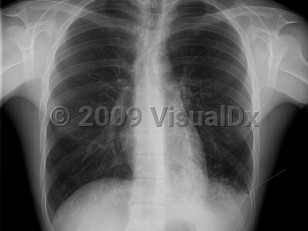

Primary viral pneumonia is the complication responsible for the most influenza-related deaths. Those with pre-existing cardiopulmonary disease or who are pregnant are at the greatest risk. The initial clinical presentation is the same, but dyspnea increases in severity. Productive cough may be blood tinged. Massive hemoptysis has been reported. When severe, there may be profound respiratory distress with tachypnea, tachycardia, and cyanosis. Rales and wheezes will spread throughout the chest from the lower lung.